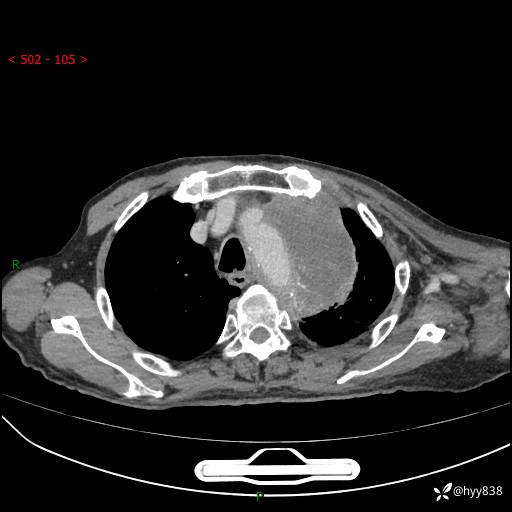

老年男性,气促5月,胸背痛2月。发现肺尖较大肿块,摧枯拉朽之势---结果公布~

现病史:患者于5月前饮酒后突发静息状态下气促不适,无胸闷、胸痛、发热、咳嗽、咳痰等不适,于当地第五人民医院及我院就诊,输液治疗后(具体不详)后气促稍缓解,遂出院后自行口服中草药治疗。近2月出现胸背痛,伴左上肢疼痛、乏力、感觉异常,稍有咳嗽、咳痰,咳黄痰、痰液粘稠,无咳血。为进一步诊治来我院。

胸部CT增强扫描(外院平扫)